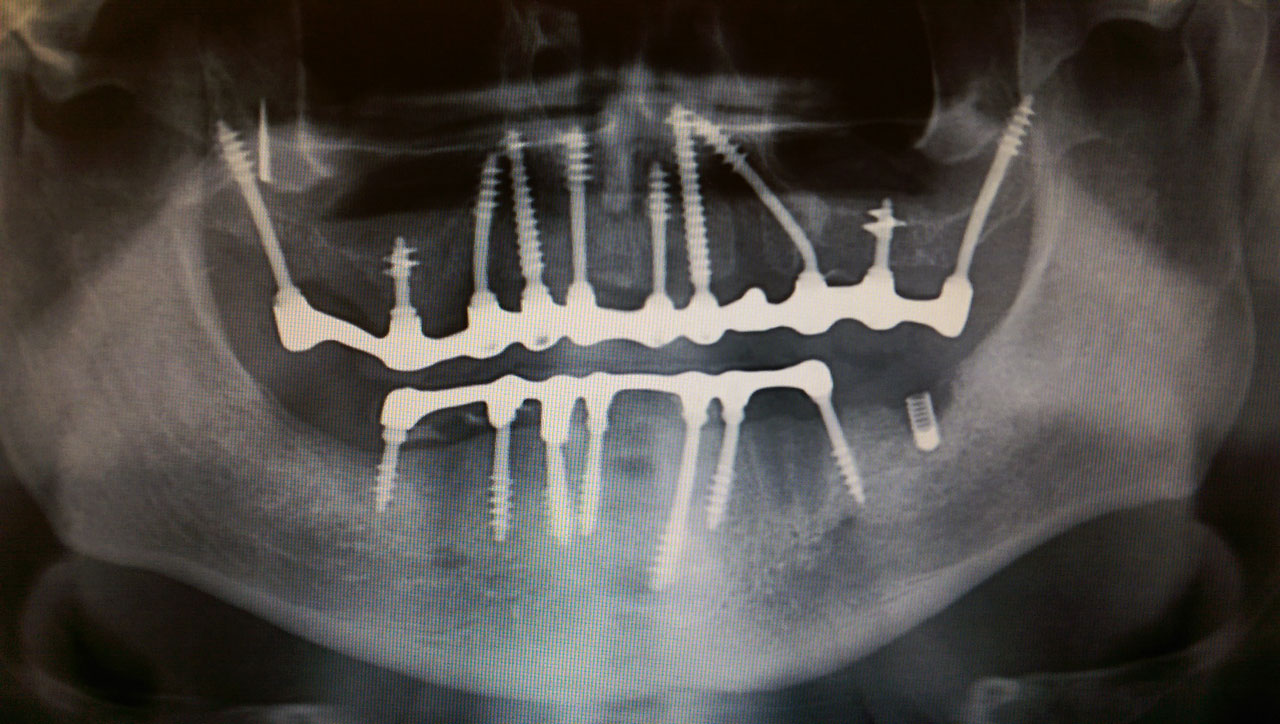

2 nap alatt varázsoltuk ezt a szép esztétikus alsó, felső körhídat implantátumokkal megtámasztva a korábban elhanyagolt szájba. Az 1. nap 26 fogat távolítottunk el, mert annyira rossz állapotban voltak, és rögtön azonnal terhelhető IHDE svájci implantátumokat raktunk be, fentre 8, lentre 6 darabot. A sebeket összevarrtuk és intraorális szkennerrel digitális lenyomatot vettünk. 2 nap múlva pedig beragasztottuk a kész PMMA műanyag körhidakat. Dr. Kelemen Péter és a Symbion Fogtechnika munkája.

Teljes fogatlanság helyreállítása 2 nap alatt azonnal terhelhető svájci IHDE implantátumokkal és PMMA műanyag hidakkal. Intraorális szkennerrel vettünk lenyomatot az implantáció után, és erre a digitális mintára készítette el a fogtechnika a hidak digitális tervezését, majd faragta ki műanyagból. Ezt a gyors munkát az azonnal terhelhető implantátumok és a digitális lenyomat, tervezés segítségével tudtuk megcsinálni mindössze 2 nap alatt. Dr. Kelemen Péter és a Symbion Fogtechnika munkája.